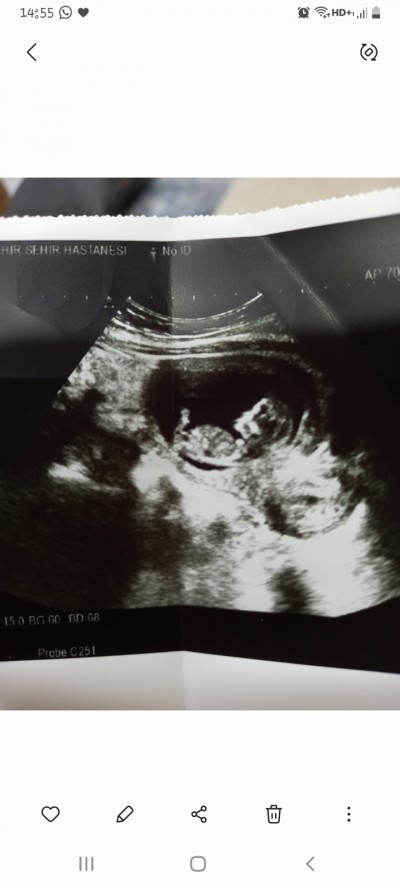

Henüz erken biliyorum ama insan merak ediyor rica etsem tecrübeli annelere tahminde bulunabilir mj acaba :) biraz önce yüklemeye çalıştım ama sanırım becemeredim:)

Kıza benziyor ☺️

Erkek geldi içimden:)

❣❣❣❣kiz bebek hissettim

Erkek geçti içimden sağlıkla kavuş canım

Kız diyorm